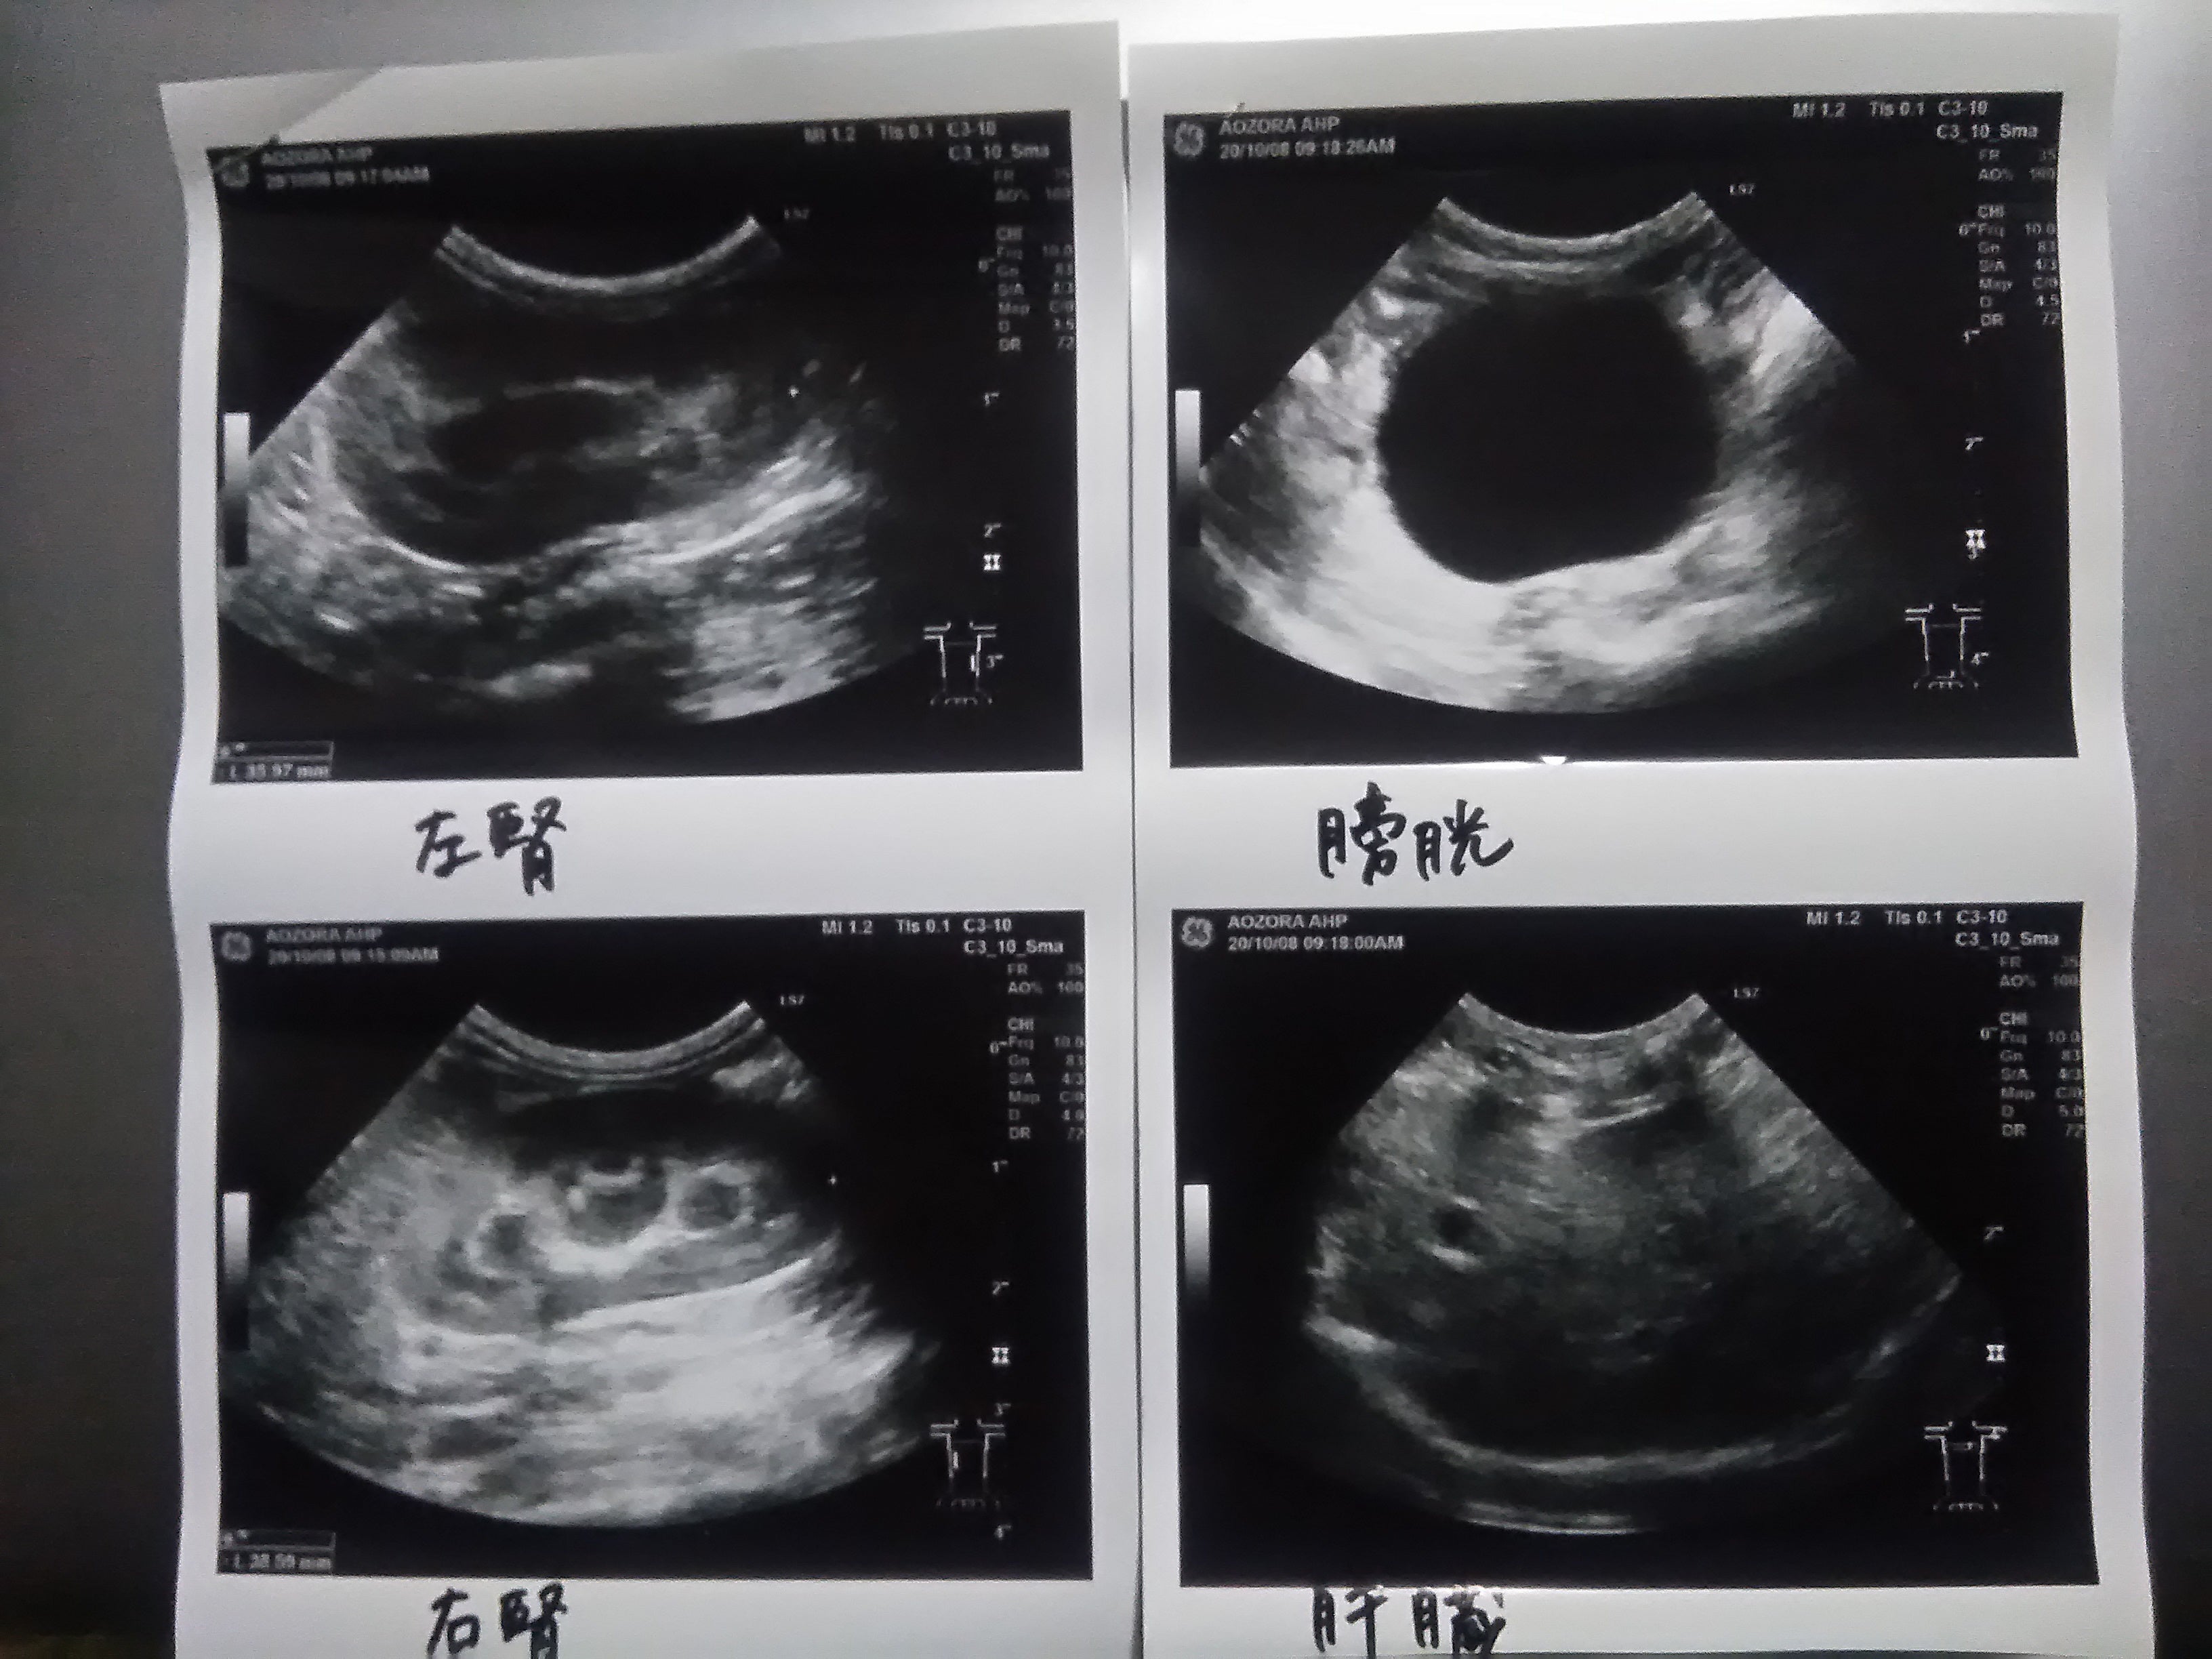

その他の数値も順調に良くなっていたのですが、何よりも良かったことが、お腹に溜まっていた腹水が、ほぼ完全になくなったことです!

腹水が溜まっていると、臓器が押しつぶされ、最悪の場合、呼吸困難に陥るらしいです。2週間前のペンタは、明らかにお腹がパンパンに張っていて、とても辛そうでしたが、それがほぼ無くなったというのは、心の底から安心しました。